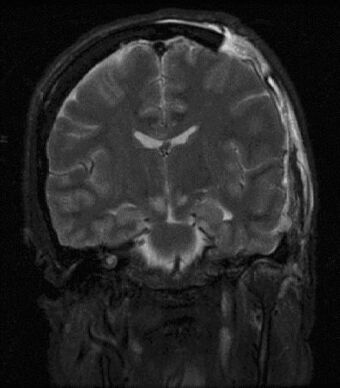

Brain herniation MRI.jpg

Severely high ICP can cause the brain to herniate.

One of the most damaging aspects of brain trauma and other conditions, directly correlated with poor outcome, is an elevated intracranial pressure.[8] ICP is very likely to cause severe harm if it rises too high.[9] Very high intracranial pressures are usually fatal if prolonged, but children can tolerate higher pressures for longer periods.[10] An increase in pressure, most commonly due to head injury leading to intracranial hematoma or cerebral edema, can crush brain tissue, shift brain structures, contribute to hydrocephalus, cause brain herniation, and restrict blood supply to the brain.[11] It is a cause of reflex bradycardia.[12]